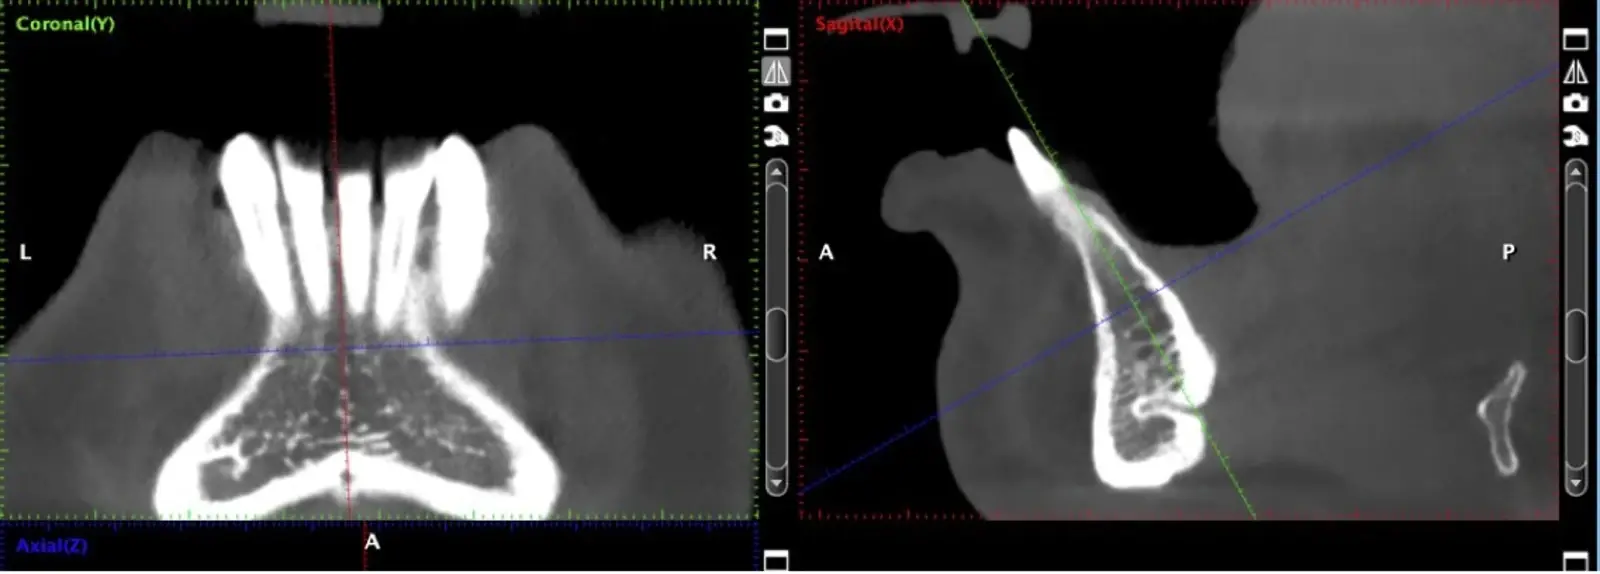

Figura 2. Evaluación de la tomografía computarizada donde se observa la presencia de un conducto vascular de riesgo a ser considerado.

Si la zona donadora es la rama mandibular, una vez realizado el decolado (Figura 4), se procede a realizar la osteotomía con los insertos de corte, según la accesibilidad se escoge el inserto angulado (Figura 5) o recto (Figura 6). Iniciamos con el corte horizontal que va desde la zona retromolar hacia mesial hasta unos 5 mm próximos a la última pieza dentaria, este corte se realiza con el inserto recto, luego se realizan osteotomías verticales. Finalmente, se realiza la osteotomía horizontal inferior con el inserto angulado del lado correspondiente, pero se debe determinar previamente en la tomografía la distancia al nervio dentario inferior, para evitar dañarlo por proximidad.

La osteotomía con insertos de piezoeléctrico nos permite un corte más definido con menor pérdida de hueso residual, ya que los insertos son extremadamente finos (0.25, 0.40 y 0.50 mm) (Figuras 7 y 8).